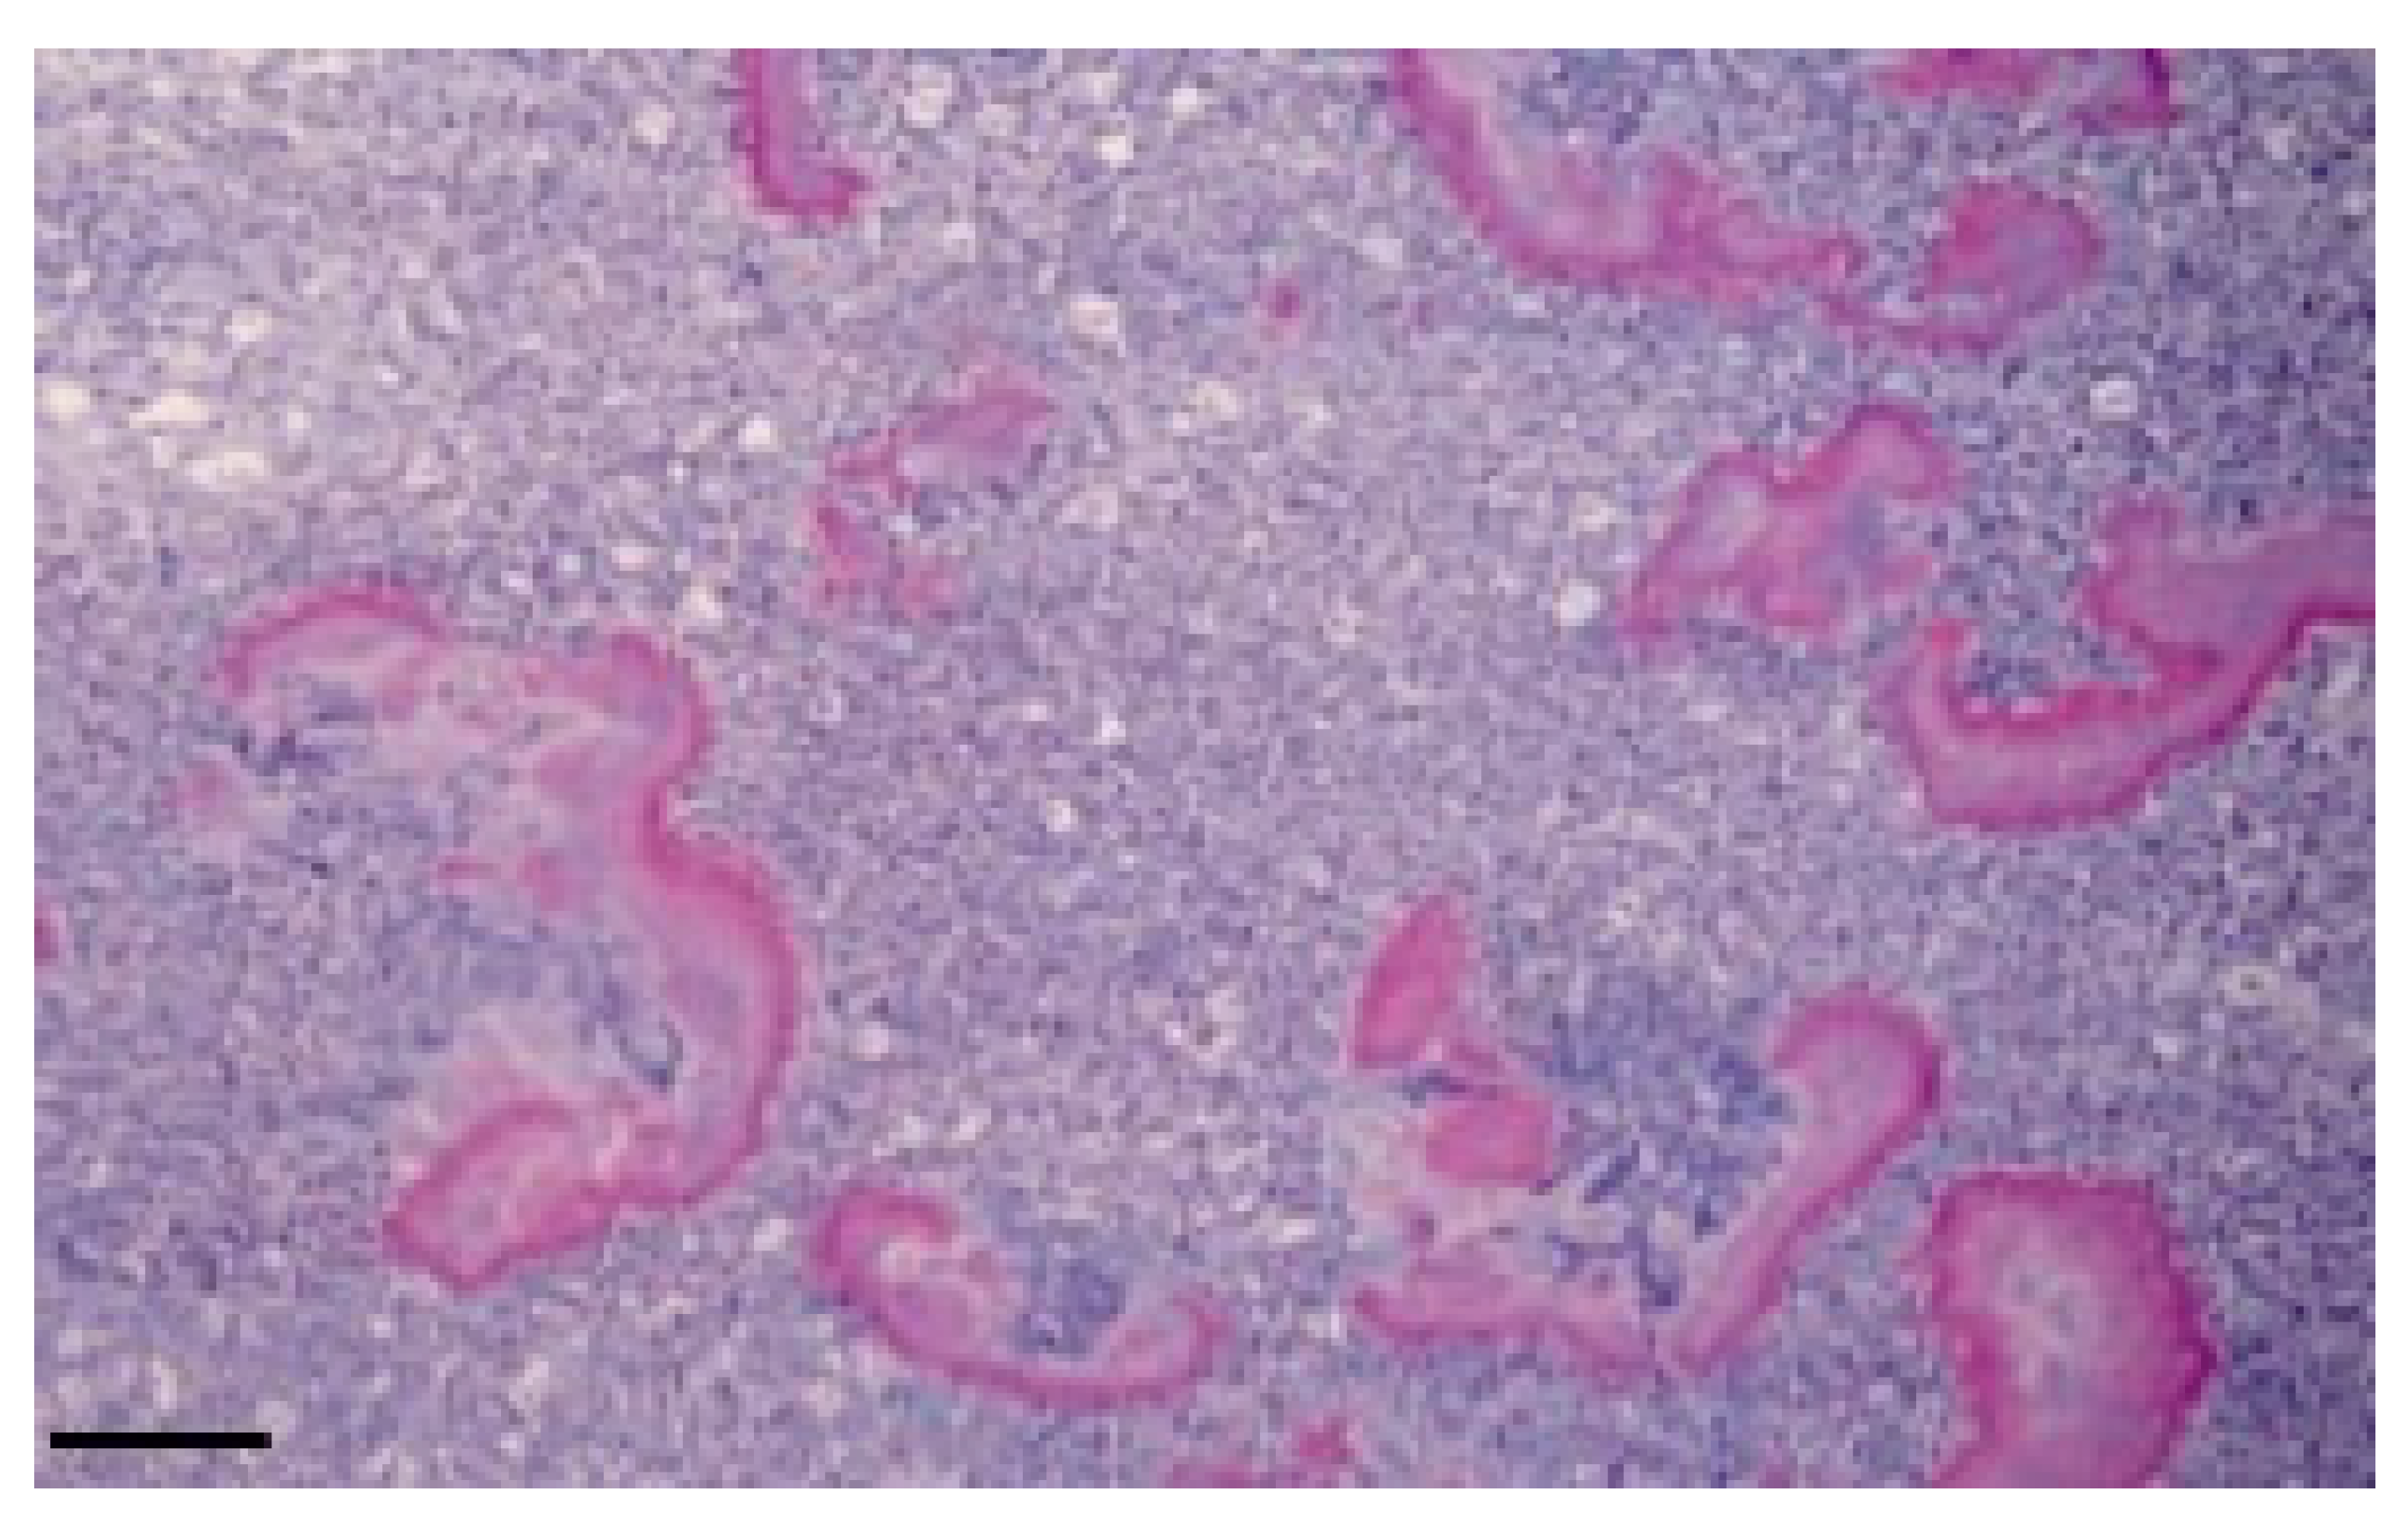

Histological examination revealed a loose connective tissue with scattered foci of granulomatosis. The granuloma is characterized by a mass of small aggregates of bacteria surrounded by numerous neutrophils, macrophages, plasma cells and some giant cells and by a wall of granulation tissue which developed into a connective tissue. The tissue was surrounded by eosinophilic club-like bodies. In addition to the granulomatous reaction, the Splendore–Hoeppli phenomenon was observed, characterized by hyaline, acidophil (Figure 3), and PAS-positive material (Figure 4) which is arranged as a crown of clavate protrusions around each colony. Gram stain was then carried out and results were Gram-negative bacteria.

Figure 4. Granulomatous reaction results to be PAS-positive and the material arranged as a crown of clavate protrusions around each colony. (brain; PAS). Bar: 10 μm.